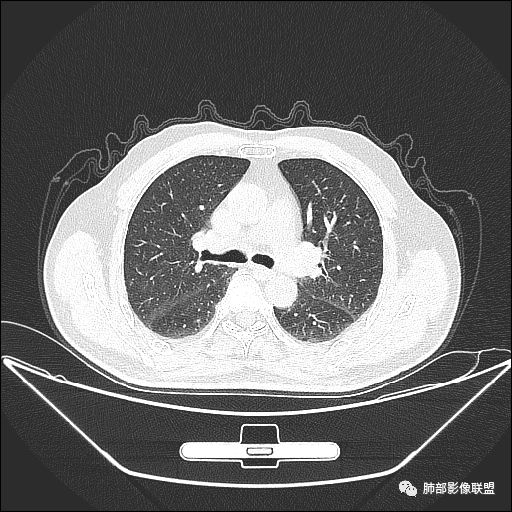

静脉期

老年男性,因“咳嗽咳痰1月余。”入院。病程中咳嗽咳痰,咳黄白痰,间断咯少许鲜红色痰血。PPD阳性。胸CT:右肺中叶外侧段支气管管腔阻塞,大片实性病变,病灶边缘光滑,部分边缘膨隆,可见分叶,肺门及纵隔可见肿大淋巴结,并可见钙化。增强可见病灶明显强化,而且延迟强化明显,病灶内多发低密度区,内见血管影,血管变细、部分血管破坏。考虑恶性病变可能性大,鉴别慢性肉芽肿性病变。

胸CT:跨叶大肿块,主体在中叶,右中叶外侧段支气管阻塞,病灶部分边缘膨隆,可见分叶,部分边缘平直,肺门及纵隔可见肿大淋巴结。增强病灶不均匀强化,延迟强化明显,病灶内多发低密度区,内见血管飘浮,部分血管变细、模糊。考虑:恶性病变可能性大,大细胞?淋巴瘤?鉴别慢性肉芽肿性病变。

右肺中叶软组织肿块,外围向内生长,叶间胸膜向前内移位,肿块近肺门侧跨叶,中叶外侧段支气管截断,密度不均匀,双侧肺门及隆突下见肿大淋巴结,增强后呈中度不均质强化,肺动脉供血,多发坏死区,边界尚清,坏死区域内见结构,结合病史考虑恶性,鉴别诊断1结核,爬行征是沿支气管树分布,外宽,内窄,周围有卫星灶,内气管狭窄后扩张,此例沿叶间胸膜长轴分布,气管有截断,不典型。2炎性肉芽肿,符合的地方下方层面增强后延迟性轻度环形强化,不符临床无发热等急性感染病史,实验室指标不符,病灶周围渗出及慢性炎性改变有,不明显。

这个支气管是走形通畅,但是壁增厚的。比较符合炎症改变

内侧段是通畅但是受压的

外侧段一开始狭窄

但是远端通畅,所以我认为支气管都没有堵塞,不太可能是鳞癌

病灶明显平直,中央是粘液栓,低密度,分界清楚

吴婧老师和南边老师都对该病例进行了深入分析。从支气管管壁的增厚,支气管狭窄后扩张,支气管粘液栓,病灶形态,到病灶不均匀强化及坏死彻底,到周边病灶及肺组织空气的潴留,加之纵隔内淋巴结肿大伴钙化等等,都支持慢性炎性病灶,尤其是结核。

墨西哥仙人掌征---结核        影像上结核灶,粗大的均匀枝干,推测是支气管囊状扩张引起的,在非支气管区,形成圆形坏死囊群;如果这些坏死比较稀薄,又遇到扩张支气管,就会形成粗大的“墨西哥仙人掌”。结核引起的支气管近端炎症纤维化,可以造成支气管阻塞,从而将干酪样坏死物封堵在管腔内。仙人掌主干内部应该是干酪为主,稀薄的,具有流动性,时间久了会出现钙化。